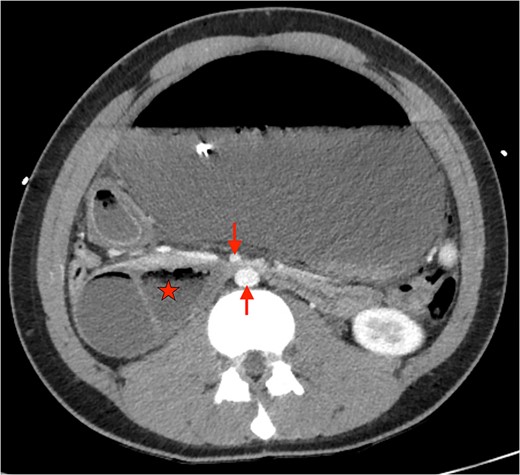

An 18-year-old male presented with severe abdominal pain, distension, and vomiting after a buffet meal. He had a BMI of 22 (weight 71 kg, height 181 cm) and no significant medical history or recent weight loss. He was normotensive (110/80), tachycardic (>120 bpm), and febrile (38.9°C). Examination revealed lethargy, a grossly tympanic, distended and tender abdomen. Biochemical tests showed severe lactic acidosis (pH 7.13, lactate 13.7), leukocytosis (white cell count 21×108) and acute kidney injury (creatinine 203 μmol/L, glomerular filtration rate 40 ml/mn/1.73m2). CT scan revealed acute gastric dilatation (35×19×12 cm), gastric pneumotosis and portal venous gas (Figs 1 and 2) with aortomesenteric angle of 5° and distance of 6 mm (Fig. 3). There were broad differentials considered at the time of presentation including both mechanical and functional aetiologies (Table 1).

Axial CT showing severely distended stomach and dilated duodenum with transition point between SMA and aorta. (★: Duodenum. ↓: Superior mesenteric artery. ↑: abdominal aorta).